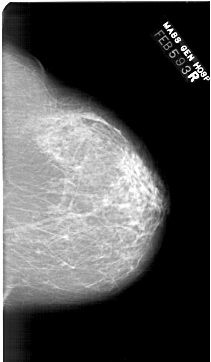

A_1443_1.RIGHT_CC

RIGHT_CC LINES 6511 PIXELS_PER_LINE 3781 BITS_PER_PIXEL 12 RESOLUTION 43.5 NON_OVERLAY